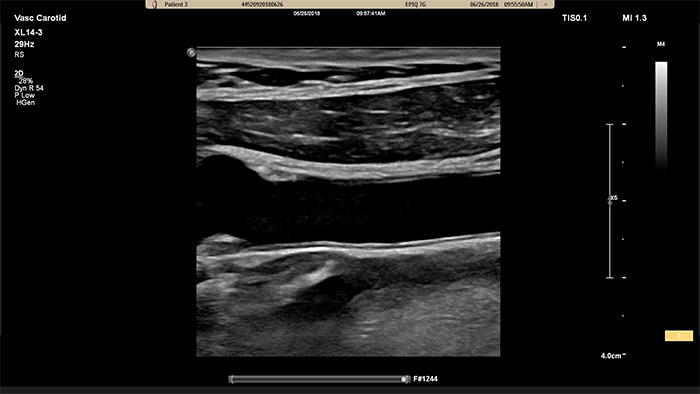

O transdutor XL14-3 xMATRIX incorpora uns 14 000 elementos incríveis, todos ligados a um microcanal separado. O transdutor XL14-3 possui focagem eletrónica multidimensional para a imagiologia de cortes ultrafinos da anatomia vascular e morfologia das placas.O principal benefício: excecional confiança no diagnóstico ao avaliar a estenose e placas vulneráveis.